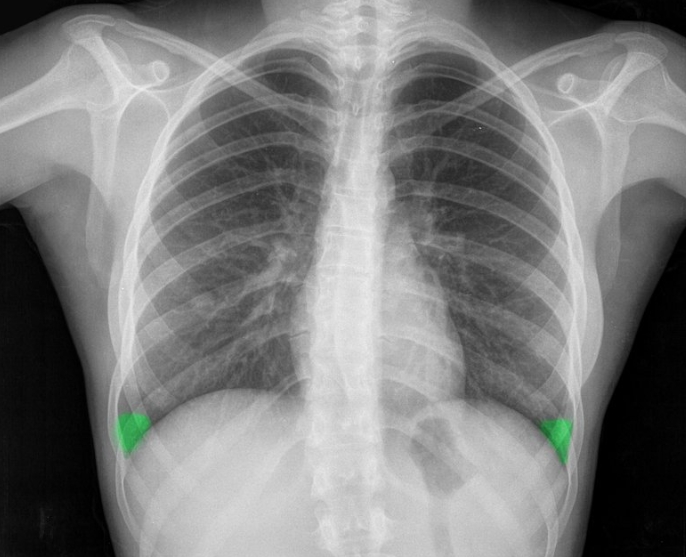

엑스레이를 보면 검고 하얀 그림처럼 보여요. 검은 부분은 공기가 많은 곳, 하얀 부분은 단단한 조직이에요. 이런 밝고 어두운 차이를 ‘음영’이라고 부릅니다. 폐처럼 공기가 가득한 부위는 검게, 뼈는 하얗게, 그리고 물이나 염증이 차면 회색빛으로 보이지요.

한번은 가족 중 한 분이 감기인 줄 알고 병원에 갔는데, 엑스레이를 본 의사 선생님이 “오른쪽 아래 음영이 진하네요”라며 흉부 엑스레이로 알수있는것 폐렴을 의심하셨어요. 실제로 약간의 염증이 있었던 거죠. 이렇게 음영은 그림자처럼 보여도, 그 속엔 우리 몸의 변화가 담겨 있어요. 뿌연 음영이 작게라도 생기면 “왜 그런 걸까?” 하고 한 번쯤 더 살펴볼 필요가 있습니다.

엑스레이 한 장으로도 알 수 있는 게 많습니다. 흉부 엑스레이로 알수있는것 폐렴, 결핵, 기흉(공기가 새어나온 상태), 폐수종(폐에 물이 찬 상태), 심비대(심장이 커진 상태), 늑골 골절, 흉막삼출(가슴 안쪽에 물이 고인 상태) 등 다양한 질환의 단서를 볼 수 있죠.

폐렴은 엑스레이에서 가장 자주 발견되는 질환 중 하나예요. 정상적인 폐는 까맣게 보이지만, 염증이 생기면 하얗게 변합니다. 의사들은 이를 보고 ‘침윤(염증이 번진 상태)’이라고 표현해요.

흉부 엑스레이로 알수있는것 폐렴의 종류에 따라 모양도 달라요. 한쪽 폐 전체가 하얗게 보이면 ‘엽성 폐렴’, 군데군데 얼룩처럼 보이면 ‘기관지 폐렴’일 수 있어요. 예전에 제 친구가 독감 후 기침이 너무 오래가서 병원에 갔는데, 엑스레이에 하얀 구름처럼 음영이 보여 폐렴 진단을 받았죠. 약을 꾸준히 먹고 다시 찍었을 땐 그 구름이 걷힌 것처럼 깨끗했어요. 이렇게 눈에 보이는 회복의 흔적이 참 다행스럽습니다.

엑스레이 결과지를 받으면 처음엔 알아보기 어렵지만, 구조적으로는 규칙이 있어요. 폐는 공기로 가득해 검게 보이고, 심장은 가운데 밝게 자리하죠. 만약 폐 안에 뿌연 부분이 생기면 염증, 액체, 혹은 출혈을 의심하고, 반대로 너무 까맣게 보이면 기흉일 수 있어요.

의사들은 ‘폐야, 심장이야, 갈비뼈야’ 하며 차근차근 확인합니다. 심장이 커져 있으면 고혈압이나 심부전의 가능성을 생각하고, 횡격막이 들려 있으면 공기나 가스가 차 있을 수 있어요. 또 갈비뼈가 부러졌거나 척추가 휘어져 있으면 엑스레이에서도 바로 드러납니다. 이처럼 단 한 장의 사진에도 온몸의 이야기가 담겨 있는 거예요.